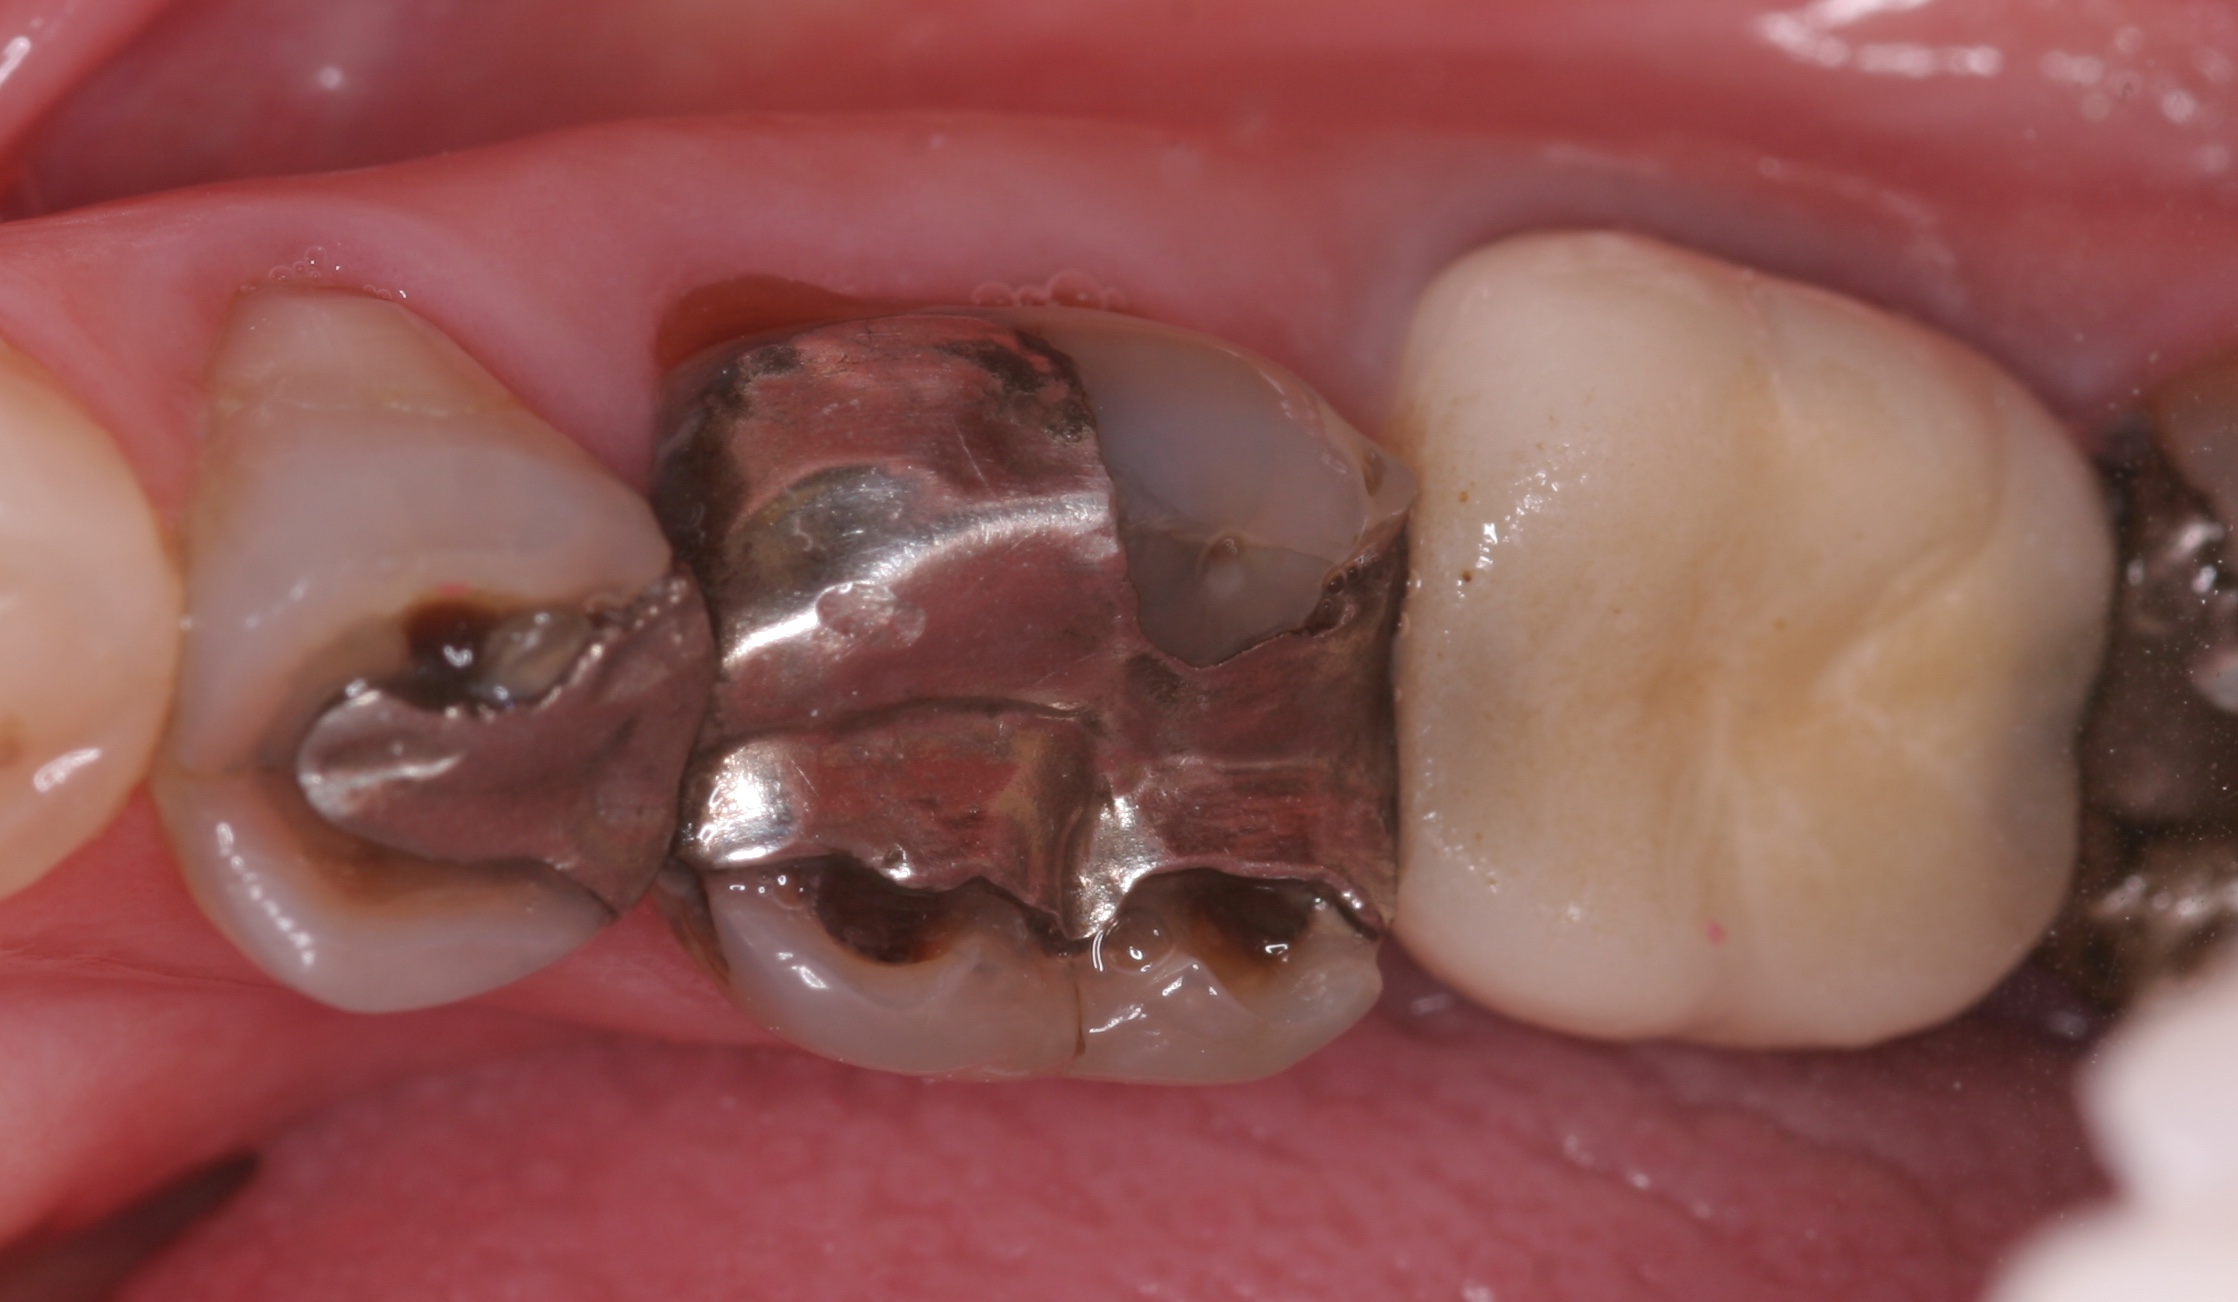

(7.) “Ditching” from GERD around existing restorations may be noted upon examination.

Figure 7